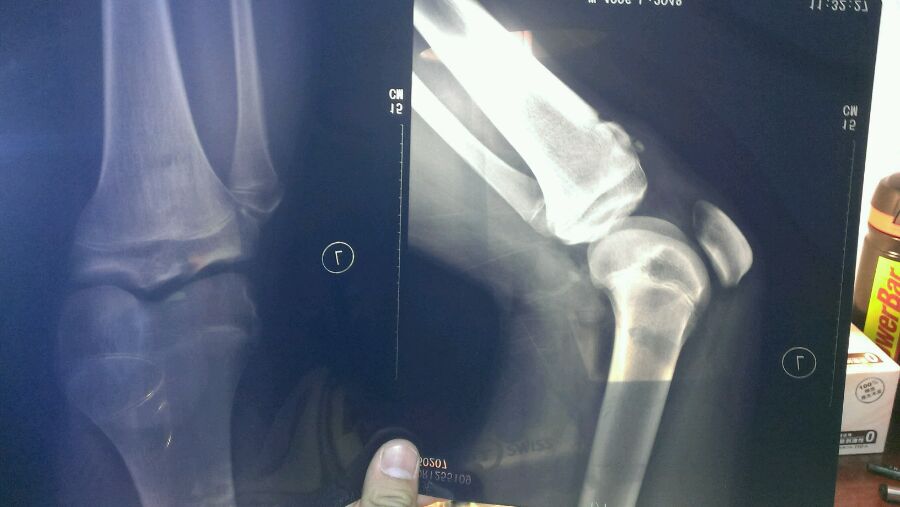

这这这………是膝盖骨移位了?

不是,我好像片子拍反了,反正就是膝盖以下凸起

股骨骨折

股骨下端那里骨质断出来了,具体不知道怎么治,还是去医院吧

楼主几岁?这是骨垢炎吗

是不是膝盖下方有一块骨头突出 碰一碰还会痛?

这是骨垢炎 大家别瞎猜了

胫骨结节骨骺炎,青少年常见,会自愈的